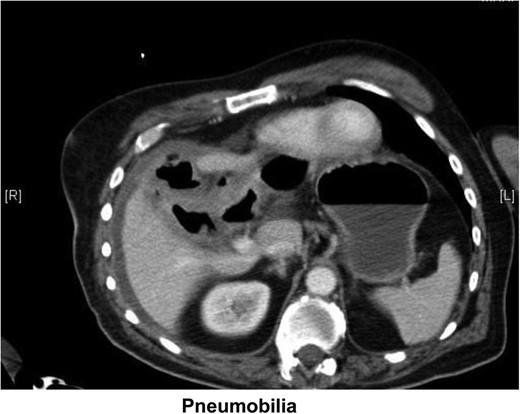

Pneumobilia with cholecystoduodenal fistula secondary to gallstone passage.

Small bowel obstruction with transition in the distal ileum probably due to obstructing gallstone (Fig. 2).